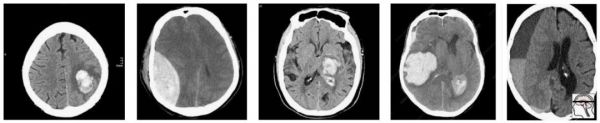

在这群人中,我们有很合理的“临床”病例组合。3 例脑内出血(可能与高血压或中风有关),2 例创伤性出血(右侧的是硬膜下出血,左侧的是硬膜外出血)。